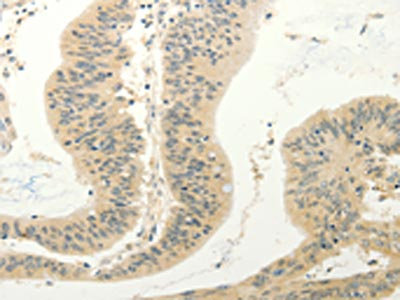

The image on the left is immunohistochemistry of paraffin-embedded Human colon cancer tissue using CSB-PA617545(FZD8 Antibody) at dilution 1/30, on the right is treated with synthetic peptide. (Original magnification: ×200)

The image on the left is immunohistochemistry of paraffin-embedded Human gastric cancer tissue using CSB-PA617545(FZD8 Antibody) at dilution 1/30, on the right is treated with synthetic peptide. (Original magnification: ×200)